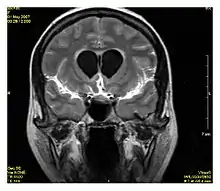

استعادة السائل الموهن بالانقلاب بعد التباين في حالة التهاب سحايا.